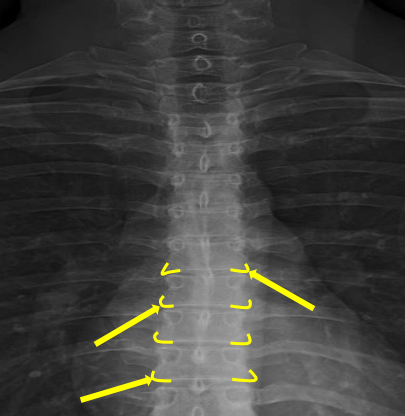

Femur heads

Superior iliac crests

Lateral iliac crests

Ischial tuberosities

Obturator foramen

S2 tubercle

Pubic symphysis

Sacral groove

Lateral aspect of sacrum

Medial aspect of ilium